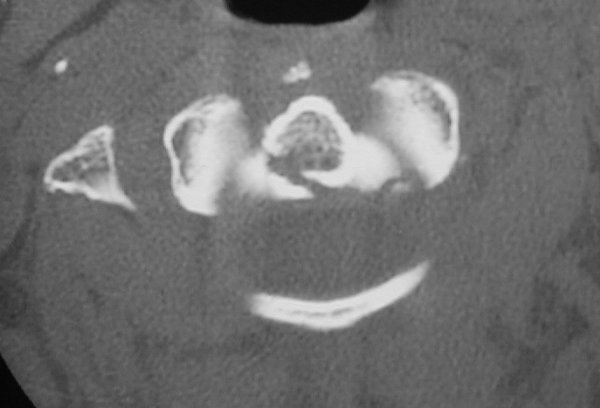

Return to Dens Fracture